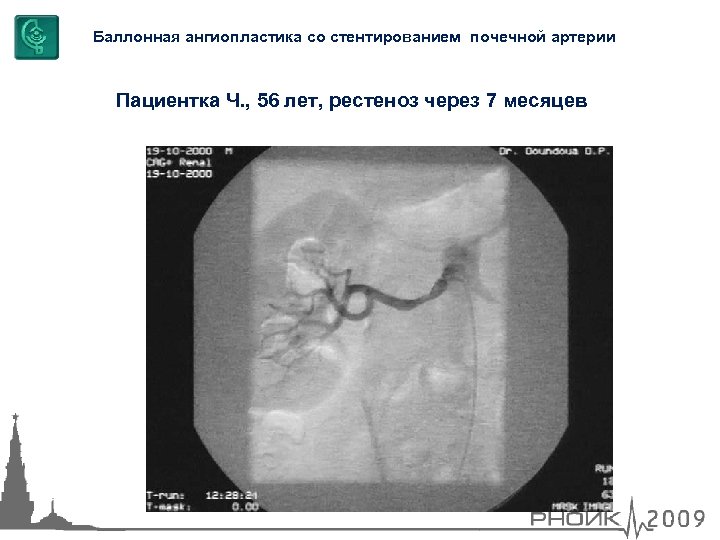

Баллонная ангиопластика со стентированием почечной артерии Пациентка Ч. , 56 лет, рестеноз через 7 месяцев

Баллонная ангиопластика со стентированием почечной артерии Пациентка Ч. , 56 лет, рестеноз через 7 месяцев